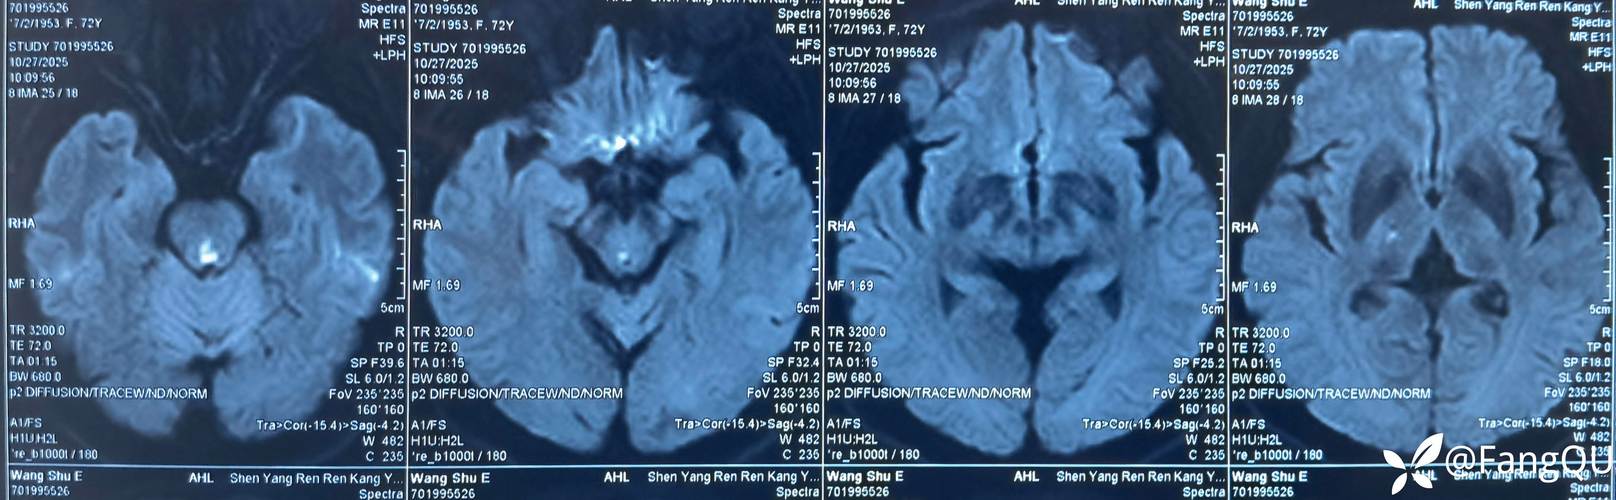

我们来理解一下“脑干梗塞”意味着什么

脑干梗塞是所有脑卒中中最为凶险、死亡率最高、预后最差的一种,梗塞的部位不同,影响的症状也不同,但通常会直接威胁到生命体征。